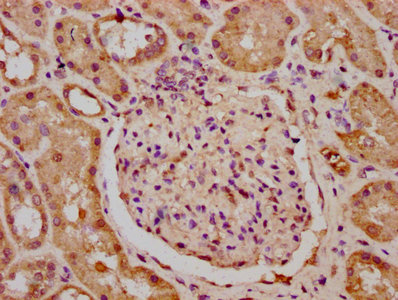

IHC image of CSB-PA23569A0Rb diluted at 1:400 and staining in paraffin-embedded human kidney tissue performed on a Leica BondTM system. After dewaxing and hydration, antigen retrieval was mediated by high pressure in a citrate buffer (pH 6.0). Section was blocked with 10% normal goat serum 30min at RT. Then primary antibody (1% BSA) was incubated at 4°C overnight. The primary is detected by a biotinylated secondary antibody and visualized using an HRP conjugated SP system.

Application Recommended Dilution IHC 1:200-1:500 -